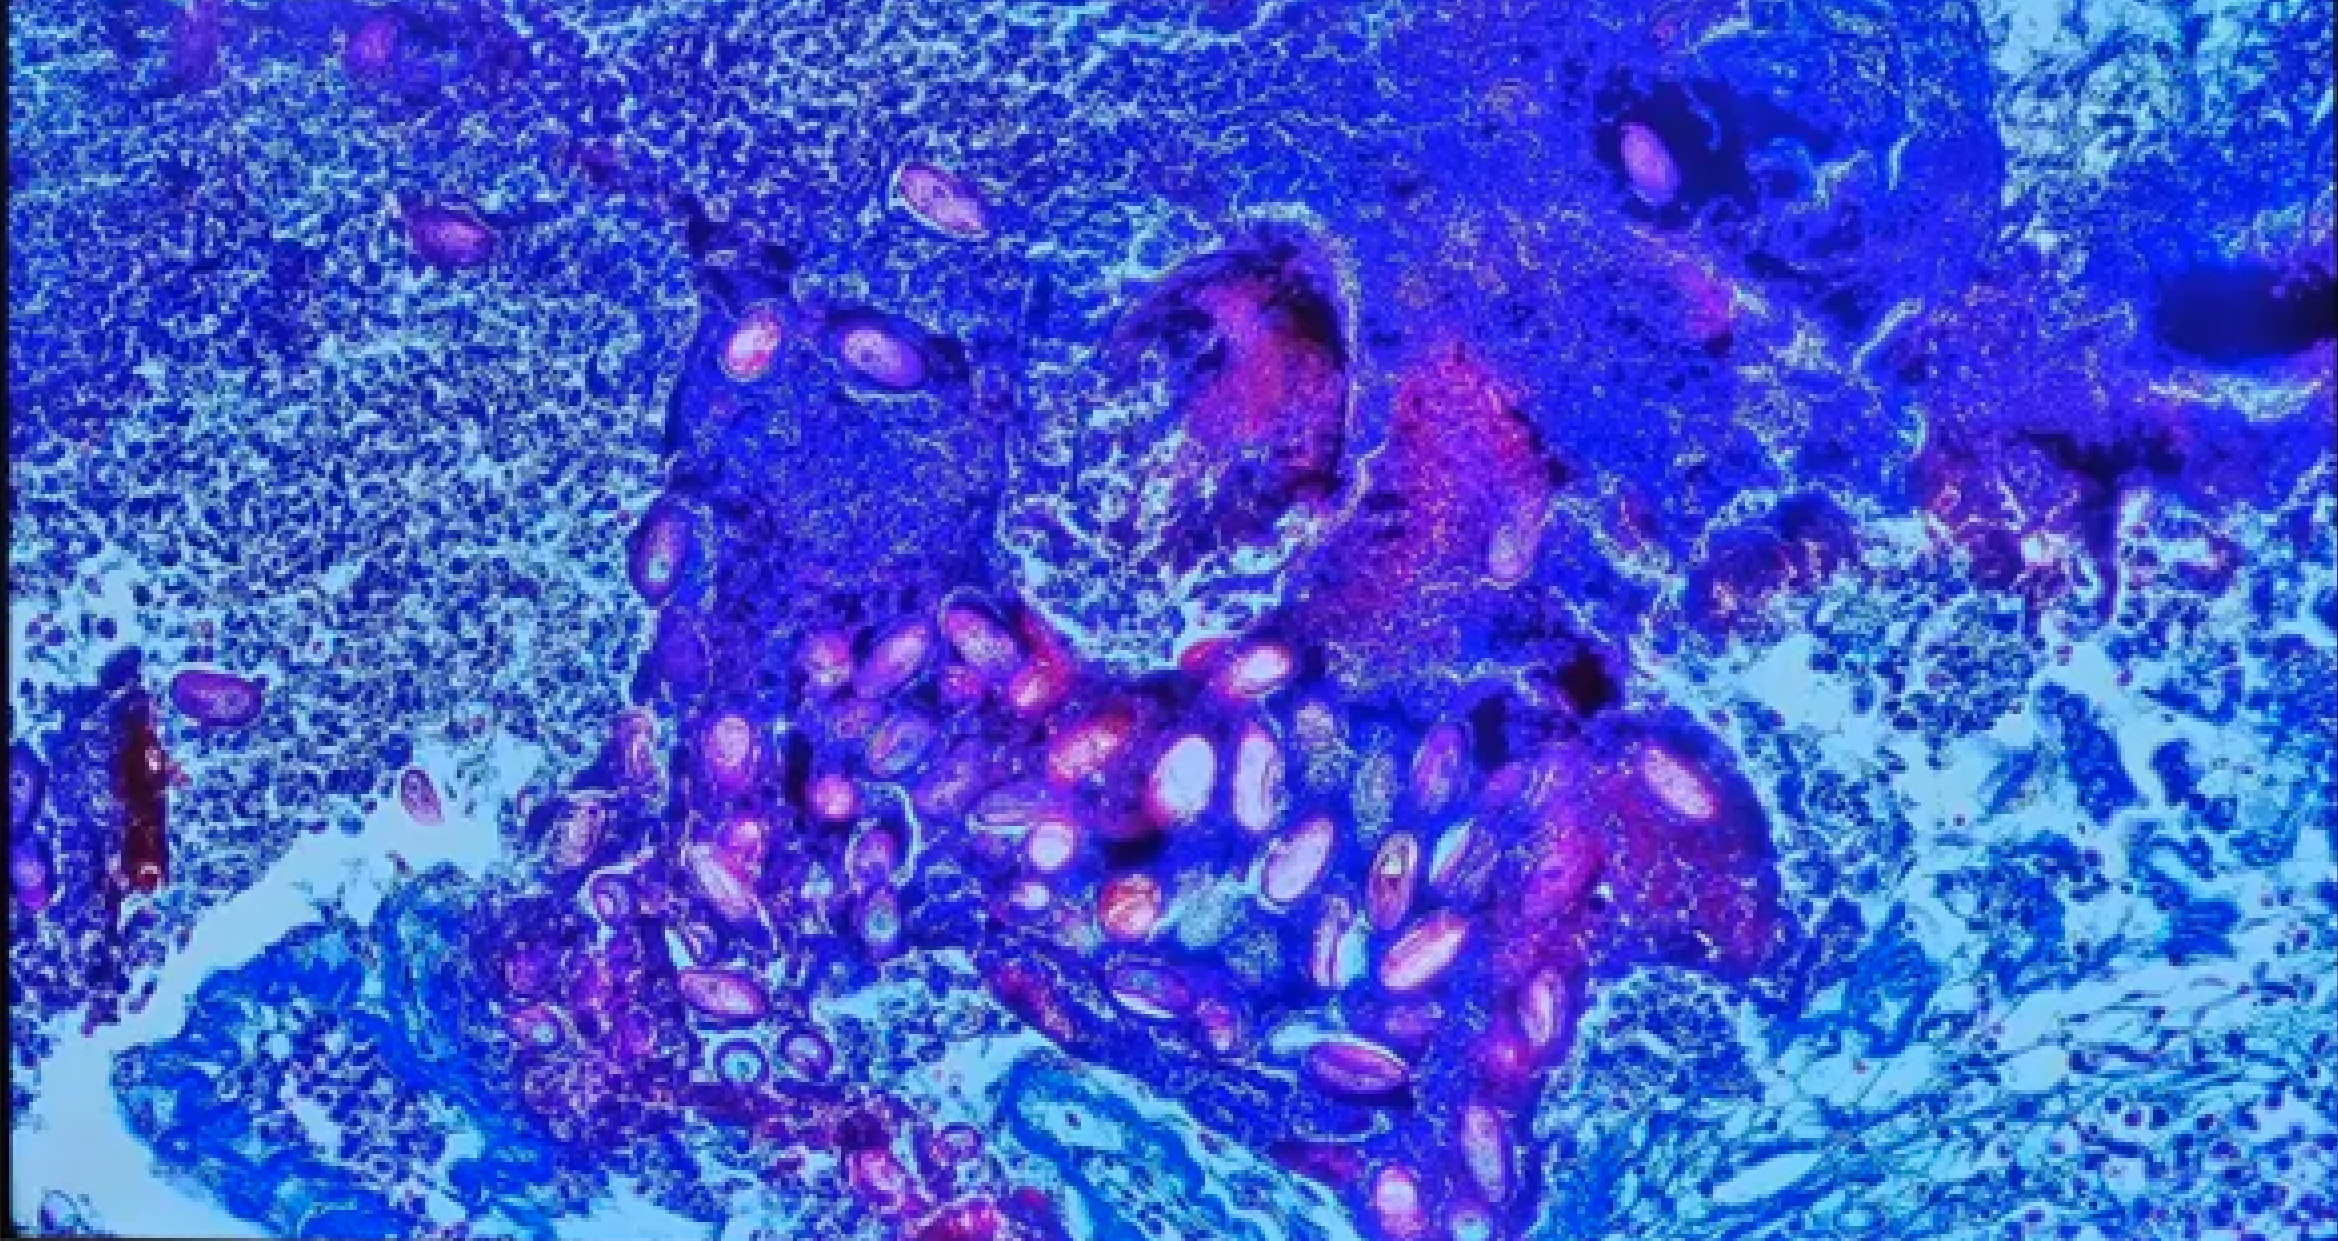

🔷🪳 Leishmania donovani (Amastigota)

😷❓ Parazytoza: Leiszmanioza

🧩🦠 Organelle:

🟣 - jądro komórkowe; wici są zredukowane i niewidoczne.